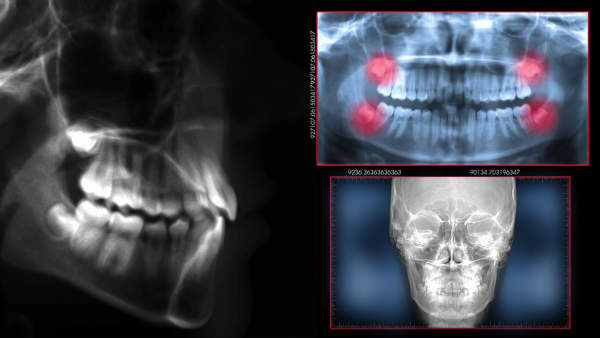

Para diagnosticar corretamente a ATM, o profissional irá realizar um exame minucioso da musculatura e tecidos da cabeça e pescoço, além da solicitação de exames radiográficos. Os sinais e sintomas são fundamentais para o fechamento do diagnóstico.

Após exame rigoroso e exames complementares (rx, ressonaria magnética,tomografia, polissonografia, exames de sangue, etc), é estabelecido um plano de tratamento.